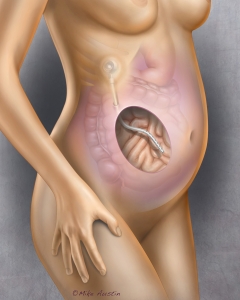

Welcome to my Patient and Professional Marketing page, where I harness the power of anatomical illustrations to educate and empower both patients and medical professionals. My unique approach combines artistry and education to convey complex surgical procedures and the utilization of medical devices in an easily understandable manner.